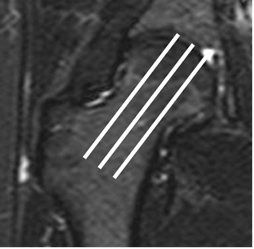

Fig 103. Orientación de cortes axiales oblicuos.

RM coronal en STIR. Los cortes deben seguir la orientación del eje del cuello femoral.